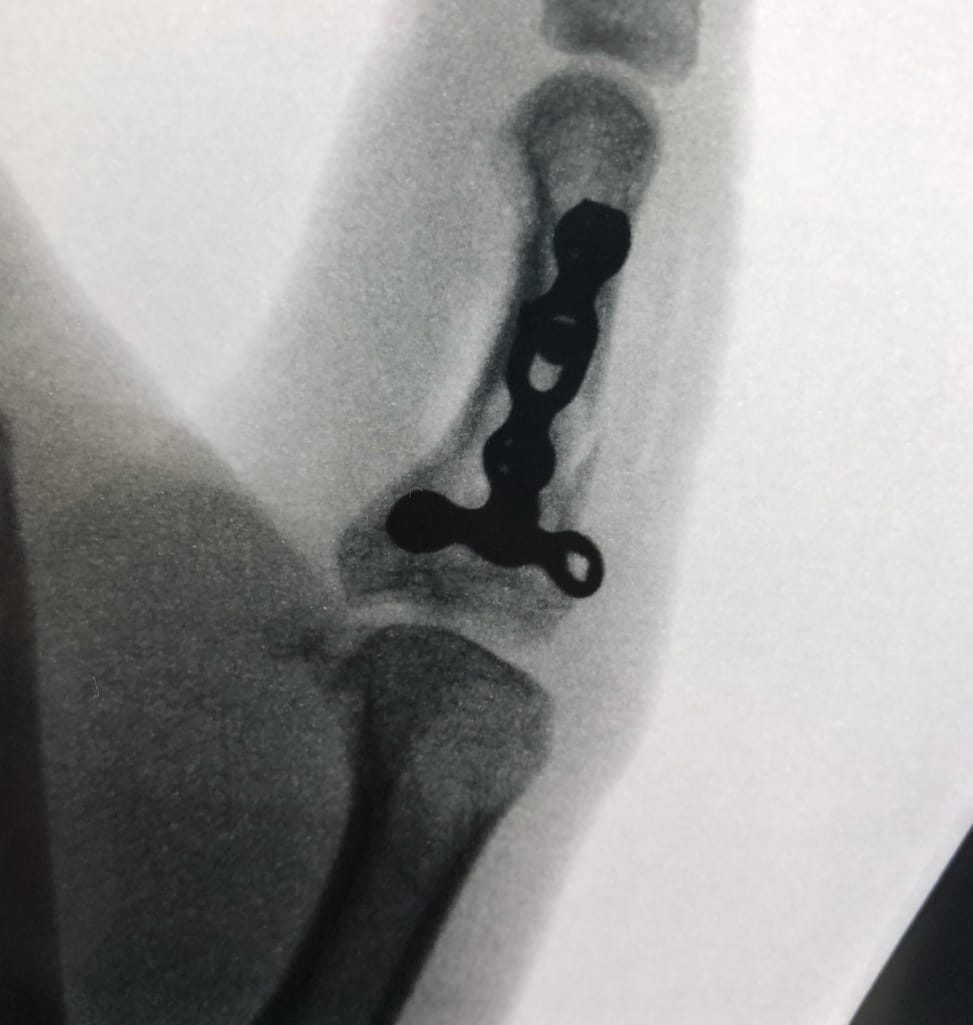

- Open reduction and internal fixation

- Minimally invasive techniques